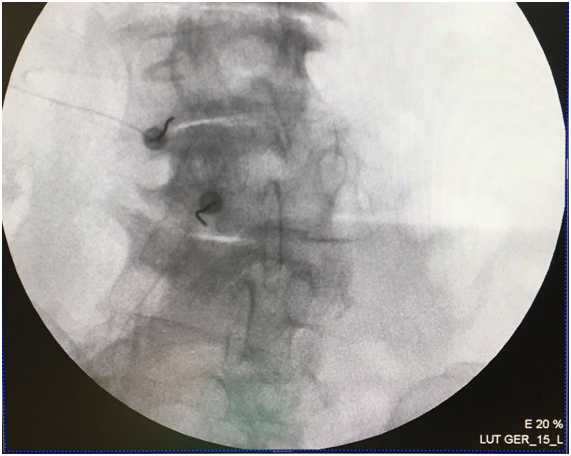

A transforaminal (TF) block was proposed at L2, L3, and L4 on the left side. After explaining the technique and its possible complications, which include the risks of infection, bleeding, and allergic reactions, oral and written consent was obtained, and the nature of the technique was explained to the patient, i.e. to perform a diagnostic block to determine the source of her pain. The technique was performed in the operating room on an outpatient basis, with standard monitoring according to SEDAR [Spanish Society of Anesthesia, Recovery, and Pain Therapy] standards (including EKG, O2 saturation, and non-invasive blood pressure tests) and radiological monitoring. The interventionist located the treatment sites with the patient lying in the prone position, using an abdominal pillow to reduce lumbar lordosis. During the procedure, a Yale 22G spinal needle was used for all treatment sites. The area was cleaned with chlorhexidine solution and misted so that the surgical field was completely sterile, with the area to be treated left exposed. A TF block was performed at the level of L2 without difficulty, although the TF block at the level of L3 was very difficult due to the patient’s anatomy, which presented with a lateral displacement of L3 and abundant osteophytes on the vertebral body, making it very difficult to visualize the entry point through the foramen. For this reason, it was deemed more appropriate to enter through the L3-L4 facet joint. In order to perform the block at this location, the C-arm of the fluoroscope was tilted obliquely until the spinous process was brought to the contralateral pedicle axis, or until the superior articular process could be seen in the middle part of the intervertebral disc, forming the famous “Scottie dog” sign, at an oblique inclination of approximately 20-30º; the double contour of the intervertebral disc was corrected with a craniocaudal inclination of the C-arm. After this maneuver, the X-ray was inclined craniocaudally (20º) to separate the iliac crest and allow entry into the foramen, according to the usual technique.13 Given the impossibility of visualizing the entry point, the C-arm was forced to incline in both directions (obliquely and craniocaudally), without achieving visualization (Figure 1). As seen in Figure 2 the only entry point that allowed access to the desired target was through the zygapophyseal joint. To perform this approach, this joint was centered and the C-arm was rotated until the facet joint could be visualized correctly. The target for this type of approach is the middle part of the joint. The approach was done in “tunnel vision” (the needle was positioned with its axis parallel to the X-rays being emitted), advancing along this direction until it reached the location of the L3 DRG. The depth of the needle was checked using a lateral X-ray view (Figure 3). The needle was pushed slightly deeper through the facet joint until it reached the epidural space and the dorsal root ganglion of L3. Entry into the joint is perceived as a loss of resistance as the needle penetrates the synovial membrane. Once it entered into the joint, the location was verified by injecting 0.1 to 0.3 mL of contrast medium (Figure 4). After verifying that the needle was placed perfectly, local anesthetics and corticosteroids could be injected. In this case, the interventionist used 0.25% bupivacaine and triamcinolone, in an amount not exceeding 1-2 mL.

Figure 2 1 Entry of the needle into the zygapophyseal joint for L3.